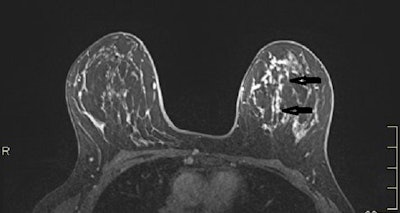

Between September 2013 and May 2019, 106 women (mean age, 57.9 years) were consecutively included in this prospective multicenter study, with 102 being retained for analysis. MRI was considered negative in the absence of suspicious enhancement and positive in cases of ipsilateral abnormal enhancement (BI-RADS 3 to 5). Final diagnoses were based on histological findings of surgical or percutaneous biopsies or at one-year follow-up.

MRI showed ipsilateral abnormal enhancement in 54 patients (53%), revealing 46 lesions requiring excision (31 benign papillomas, five papillomas with atypia, two nipple adenomatosis, and eight cancers) and eight benign lesions not requiring excision. The team found no suspicious enhancement in the remaining 48 women (47%). Forty-two were followed up at one year with spontaneous resolution of the discharge, and six underwent surgery (revealing two benign papillomas).

Overall, MRI diagnostic accuracy for the detection of a lesion requiring excision was 96% sensitivity, 85% specificity, 85% positive predictive value, and 96% negative predictive value.